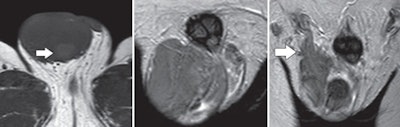

| Images are of a 40-year-old man with right testicular seminoma invading the spermatic cord. Left: Transverse T1-weighted MR image of a large right testicular tumor. The area of high signal intensity (arrow) within the lesion corresponds to histopathologic finding of hemorrhage. Center and right images are coronal T2-weighted MR, depicting a tumor of mainly low signal intensity invading the distal part of the ipsilateral spermatic cord (arrow). All images courtesy of the American Journal of Roentgenology. |